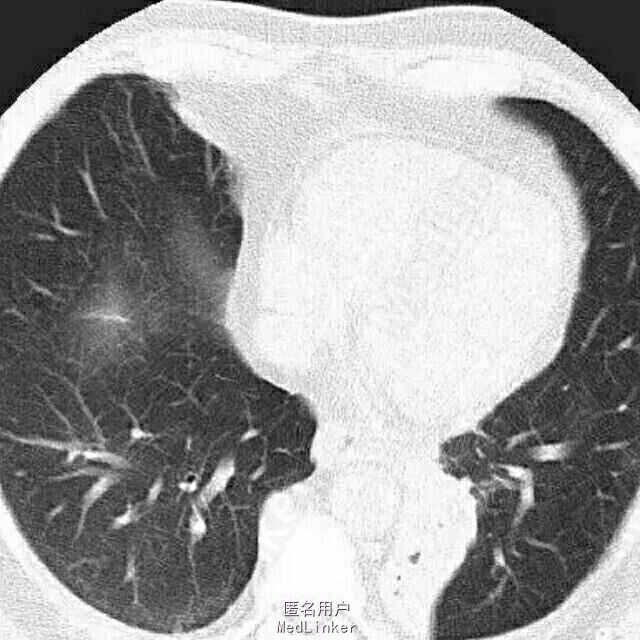

女,50岁。 间断咯血25年余,加重1月,行肺部增强CT。

患者胸部增强CT及血鬼重建影像学表现包括:边界清晰、病变有主动脉分支供血、病变静脉引流入肺静脉。

考虑影像学诊断为:肺隔离症

左肺下叶内前基底段脊柱旁可见斑片影,边界清晰,其内可见支气管气相,平扫密度尚均匀,增强后病变内强化不均匀,可见多发血管影,血管重建示病变由主动脉弓及降主动脉迂曲增粗的小分支供血,可见一直粗大静脉引流入左肺静脉。根据病变部位,供血动脉来源于体循环,静脉引流入肺静脉,此例为典型肺隔离症,已被术后病理所证实。 肺隔离症是一种先天性肺发育畸形,主要特征是部分胚胎肺组织与正常肺组织隔离,病变肺组织的动脉供应由体循环直接分出的动脉分支供应,静脉回流至肺静脉或体循环。尽管其表现多种多样,体动脉向肺组织供血为其最特征表现。常分为叶内型及叶外型2种,最常见为叶内型,多为体动脉单支血管供血,无单独胸膜包裹。叶外型有单独胸膜包裹,多位于膈肌下,由肺或体血管供血,血管较小,多伴有其他先天畸形。本例为叶内型,隔离的肺组织易反复发生感染,出现相关临床表现。 肺炎主要表现为肺实变或不张,常伴有病变周围斑片或淡片影,边界可不清晰,临床症状有助于诊断。 肺癌侵犯病变内及周围血管、支气管,造成支气管闭塞伴远端阻塞性炎症,肺门及纵隔常见肿大淋巴结。 支气管扩张伴感染时可见扩张的支气管,可为管状、串珠样或囊泡状,病变周围感染呈斑片影,边界欠清晰。